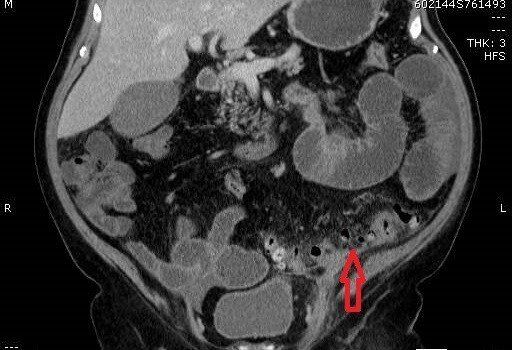

TC de abdome com contraste endovenoso fase excretora, evidenciando sinais de diverticulite aguda caracterizados por espessamento parietal do colon sigmoide, divertículos, densificação da gordura regional e presença de pequeno gás extraluminal, indicando pneumoperitônio discreto. Não há evidência de coleções pericolonicas associadas.

Na imagem, a diverticulite não complicada é caracterizada por filamento de gordura focal adjacente a um divertículo do cólon, geralmente o sigmóide. Uma pequena quantidade de líquido extraluminal e lóculos de gás podem estar presentes.

Encordoamento pericólico, muitas vezes desproporcionalmente proeminente em comparação com a quantidade de espessamento da parede intestinal

Espessamento segmentar da parede intestinal

Realce da parede do cólon

Perfuração diverticular

Extravasamento de gás e fluido para a pelve e cavidade peritoneal